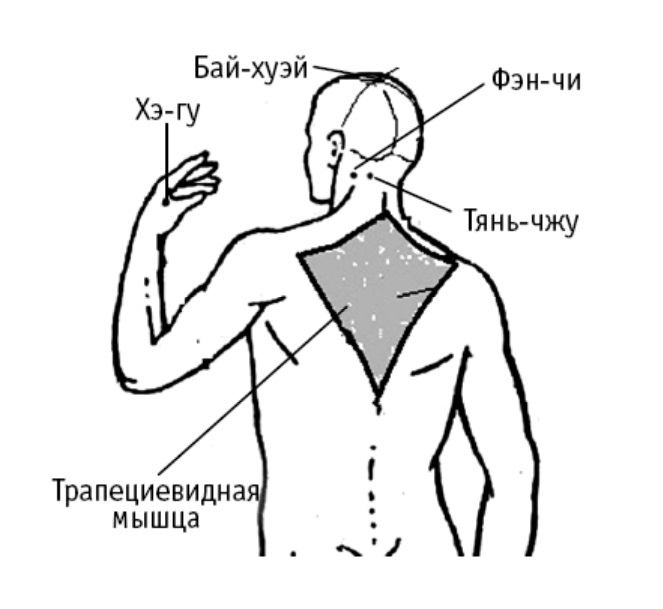

Фэн-чи («озеро ветра») расположена в углублении под черепом, напоминающем озеро, используется при лечении недугов, вызванных воздействием болезнетворного ветра (сквозняка). Вы найдете эту точку в углублении между верхними концами грудино-ключично-сосцевидной и трапециевидной мышц.

Воздействуя на фэн-чи, вы избавитесь от головной боли, головокружения, затуманивания зрения. Восстанавливается острота слуха и зрения, снижается шум в ушах.

Давлением пальца на фэн-чи в течение 3–5 минут вы сможете дополнительно снять напряжение в спине, затылочных мышцах, избавиться от болей в плечевых костях и суставах, от насморка и кашля, лихорадочного состояния, воспаления слизистых оболочек носа, горла и глаз.

Тянь-чжу («опора неба») расположена на затылочной границе роста волос, в углублении у наружного края трапециевидной мышцы на 1,3 цуня кнаружи от середины позвоночного столба.

Точку используют, когда сильные головные боли сопровождают напряжение в мышцах спины.

Хэ-гу («сомкнутое ущелье») расположена на наружной стороне кисти. Сомкните большой и указательный палец. Между 1-й и 2-й пястными костями (приблизительно в середине лучевого края 2-й пястной кости) находится точка Хэ-гу. Согласно древним канонам, ее можно использовать для уменьшения болей в теменной области головы, а также лечения болезней позвоночника и спины, снятия болей и онемения в запястье и предплечье (той руки, на которую воздействуете).

Воздействуя на хэ-гу, вы попутно будете избавляться от отечности в области шеи, насморка или носовых кровотечений, боли в горле. Точку используют для успокоения зубной боли.

Бай-хуэй («соединение пересечений») расположена в центре темени, на пересечении срединной линии головы с линией, соединяющей кончики ушей.

Воздействие на точку предотвращает головокружение, шум в ушах, помогает при частой одышке, сердцебиении, климактерических неврозах, артериальной гипертонии. Очень важная точка. Она используется так же при поносах, рвоте, недержании мочи, выпадении прямой кишки и матки, опущении внутренних органов; при солнечных ударах, потере сознания; при нервных расстройствах и др.